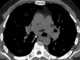

Idiopathic mediastinal cyst